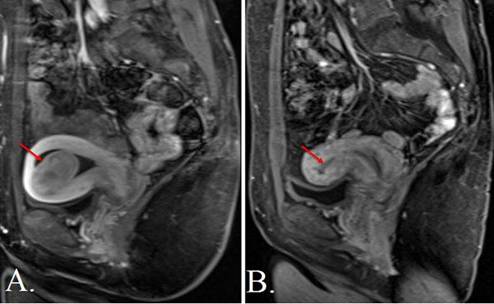

Hình 5. Hình ảnh MRI u xơ tử cung trước và sau nút mạch động mạch tử cung (UAE), vị trí khối u được đánh dấu bằng mũi tên đỏ. A. Trước can thiệp MRI cho thấy khối u xơ tử cung, tín hiệu điển hình của u xơ, trước khi thực hiện nút mạch động mạch tử cung. B. Sau can thiệp MRI sau điều trị cho thấy khối u giảm tưới máu / giảm bắt thuốc, gợi ý thiếu máu và hoại tử sau nút mạch. |